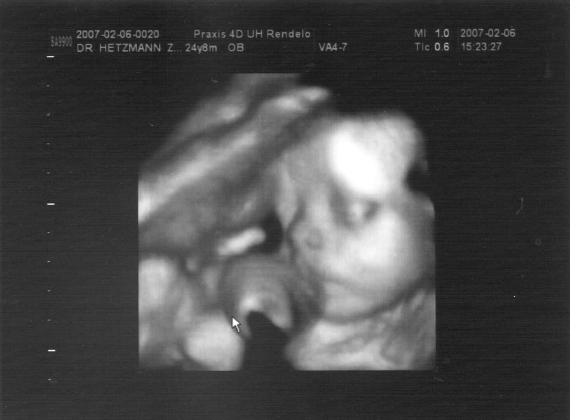

Gabi, nem tudsz valamit feltenni a 4dsből???!!!! Dvd-n van, képek is? Naggyon kíváncsi lennék!!! Én nem tudom mikor megyek/mehetek, vagy ehét vége, de gyanitom, hogy inkább febr 20 körül lesz belőle..